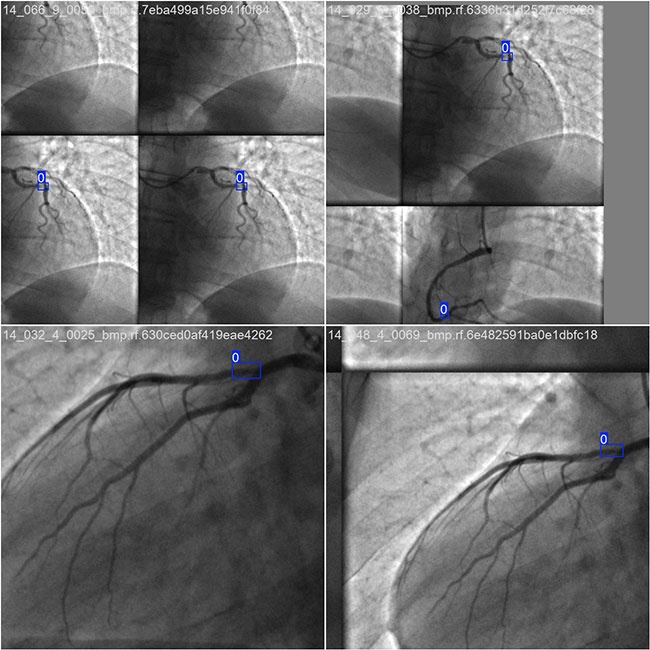

2.数据集准备与训练

本研究使用了包含狭窄性血管造影图像目标的数据集,并通过 Labelimg 标注工具对每张图像中的目标边界框(Bounding Box)及其类别进行标注。基于此数据集,采用 YOLOv8n 模型进行训练。训练完成后,对模型在验证集上的表现进行了全面的性能评估与对比分析。整个模型训练与评估流程包括以下步骤:数据集准备、模型训练、模型评估。本次标注的目标类别主要集中于狭窄性血管造影图像目标。数据集总计包含 8325 张图像,具体分布如下:

训练集:6244 张图像,用于模型学习和优化。

验证集:1665 张图像,用于评估模型在未见过数据上的表现,防止过拟合。

测试集:416 张图像,用于最终评估模型的泛化能力。

部分数据集图像如下图所示:

部分标注如下图所示:

这种数据分布方式保证了数据在模型训练、验证和测试阶段的均衡性,为 YOLOv8n 模型的开发与性能评估奠定了坚实基础。